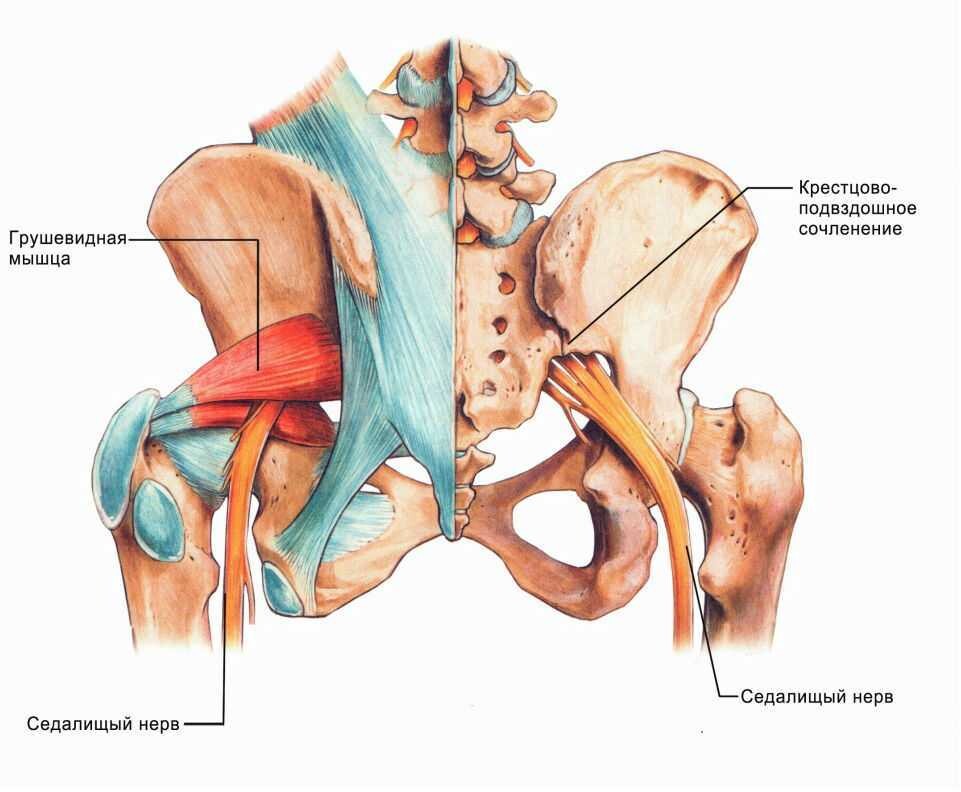

Анатомия и упражнения: Перекос таза и мышцы бедра